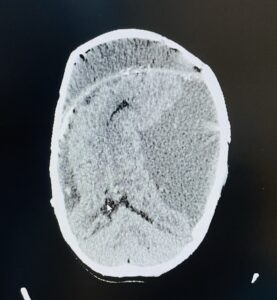

Figure 2: CT scan of brain (axial view) obtained in 2022 October, after 1st anterior vault reduction and reconstruction, yet showing significant compression of brain matter

Stage 2 – Anterior Vault Reduction and Reconstruction

An anterior cranial vault reduction was performed with mesh plate reconstruction, which significantly improved frontal bossing and cranial balance. Following this intervention, the child achieved partial head control and demonstrated improved speech, making him a candidate for further reconstructive stages.